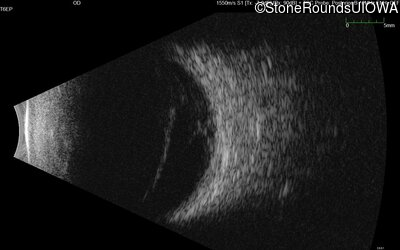

B-Scan Ultrasonography - Left - 20/200 sc

Exemplar